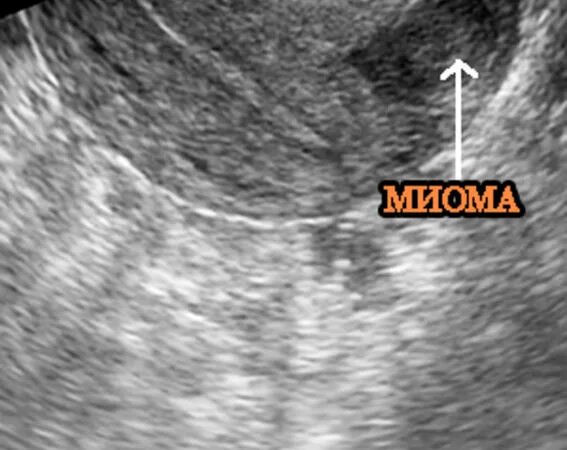

Интрамуральный узел тип 4